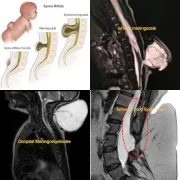

– Pediatric Spinal Conditions

– Disc Prolapse